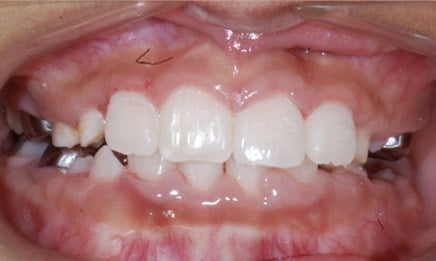

Phase 1: Kids (ages 7-10)

Beginning treatment in this phase allows us to watch the jaw as it develops to make sure it is growing in a way that will accommodate permanent teeth and improve the patient’s bite.

Phase I Treatment may or may not include braces. Your child will receive a thorough examination by the orthodontist and options will be discussed. There is never a charge for a consult with the orthodontist at Dental Town. It is all to inform and educate you on what the potential treatment options are.

At the end of Phase I, your child will receive a retainer to be worn at night time. This will last until all permanent teeth erupt, around age 12. At this time your child will be examined for Phase II treatment.

Phase I is a very important part of orthodontic treatment. Often times, if serious orthodontic problems are not caught early, it is impossible to fully achieve correction. While kids are still young, their jaws and teeth can be manipulated at a much different magnitude and speed than possible as a young adult.